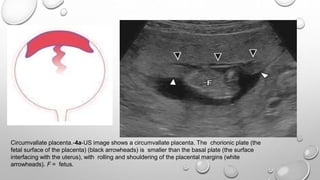

Circumvallate placenta.-4a-US image shows a circumvallate placenta. The chorionic plate (the

fetal surface of the placenta) (black arrowheads) is smaller than the basal plate (the surface

interfacing with the uterus), with rolling and shouldering of the placental margins (white

arrowheads). F = fetus.